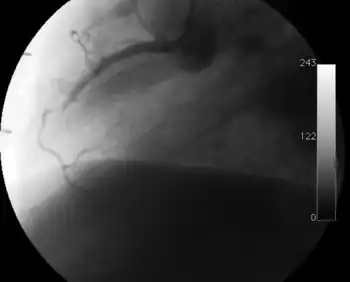

Coronary angiography

Surveillance is performed by regularly repeating coronary angiography in the cardiac catheterization laboratory, the diagnostic test of choice.[2] This is typically performed annually for the first five years after transplantation.[8] Angiography in CAV characteristically demonstrates diffuse stenoses in large coronary arteries and a reduced number of smaller coronary arteries, also known as "peripheral pruning".[2][6] However, because CAV frequently affects the entire length of the coronary artery, CAV may not be apparent by angiography alone.[2]